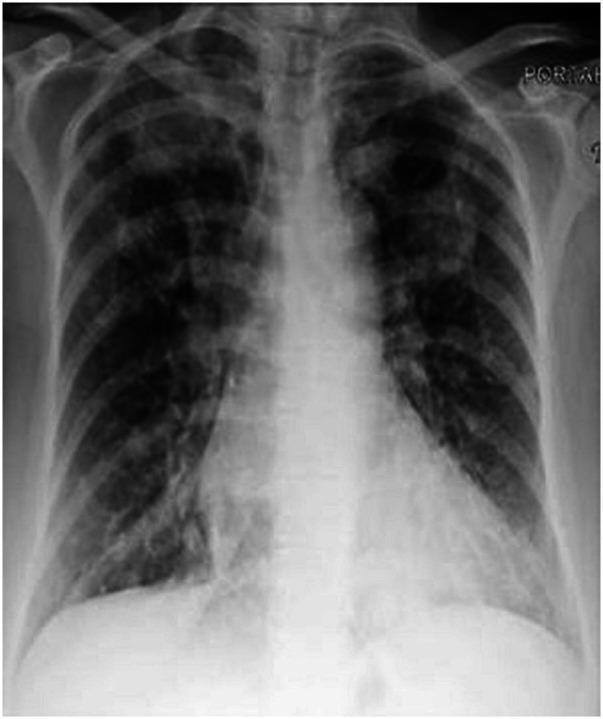

We report a rare case of a patient with Janus kinase 2-positive myelofibrosis on ruxolitinib, presenting with indolent pneumonia and cavitary lung lesions. Initial transthoracic biopsy was non-specific, but thoracoscopic biopsy revealed necrotising granulomatous disease caused by pneumonia (PJP). The patient, initially treated with trimethoprim-sulfamethoxazole, was switched to atovaquone due to gastrointestinal intolerance. Given the patient's immunosuppression and extensive cavitary lesions, an extended course of atovaquone was administered, guided by serial imaging, resulting in clinical and radiological improvement. Unfortunately, the patient later passed away from a severe SARS-CoV-2 infection before complete radiographic resolution was observed. This case highlights the importance of recognising atypical PJP presentations causing granulomatous disease in immunosuppressed patients. While rare, documenting such cases may improve diagnosis using less invasive methods and help determine optimal treatment durations for resolution of these atypical infections.

我们报告了一例接受鲁索替尼治疗的 Janus 激酶 2 阳性骨髓纤维化患者,表现为惰性肺炎和空洞性肺病变。初始经胸活检无特异性,但胸腔镜活检显示由肺炎(PCP)引起的坏死性肉芽肿性疾病。由于胃肠道不耐受,患者最初接受甲氧苄啶-磺胺甲噁唑治疗,随后改为阿托伐醌。鉴于患者免疫抑制和广泛的空洞性病变,根据连续影像学检查结果,给予阿托伐醌延长疗程,从而改善了临床和影像学结果。不幸的是,患者后来因严重的 SARS-CoV-2 感染而去世,在此之前尚未完全观察到放射学缓解。本病例强调了识别导致免疫抑制患者发生肉芽肿性疾病的非典型 PCP 表现的重要性。虽然罕见,但记录此类病例可能有助于使用侵入性较小的方法进行诊断,并有助于确定这些非典型感染的最佳治疗持续时间以达到缓解。